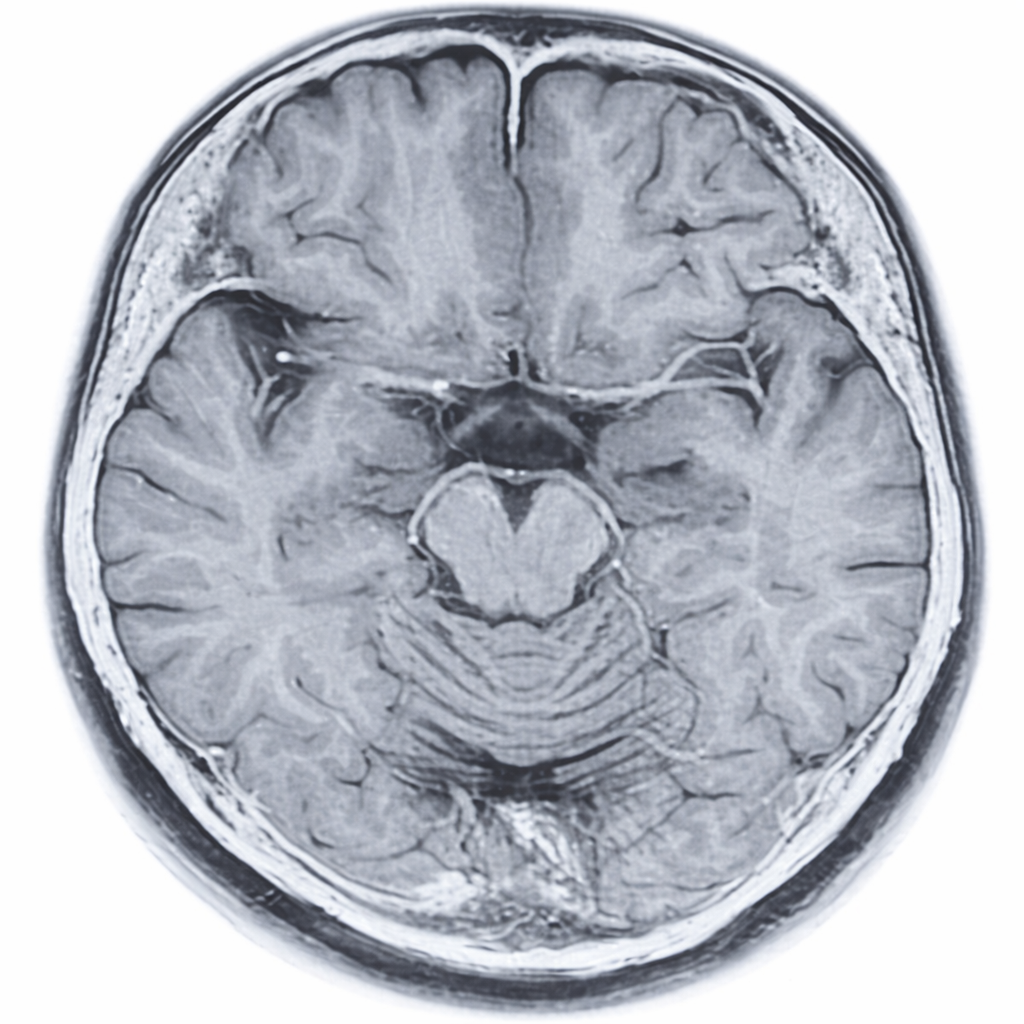

その後のCT、そして後日のMRI検査も含めて、結果は異常なし。

検査の画像を見ながら先生から説明を受けているとき、

目玉につながる2本の血管や、少し曲がっている鼻の骨を初めて見ることができました。

自分の体なのに、まるで別の人を見ているような不思議な感覚。

同時に、人間の体の神秘のようなものに触れた気がして、思わず見入ってしまいました。

先生が席を外している隙に、MRI画像の写真をiPhoneで撮っちゃいました。笑

様々な説明の後、「全く異常はありません」と言われた瞬間、心の底からホッとしました。